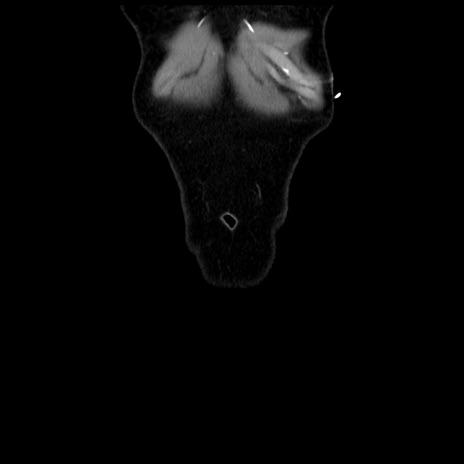

矢状断像